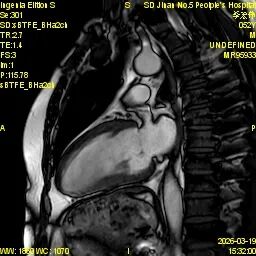

为进一步提升心血管疾病精准诊断水平,满足临床诊疗和患者就医需求,济南市第五人民医院影像科精心筹备、多措并举,顺利开展心脏磁共振(CMR)新技术,目前已完成心脏磁共振检查近30例,取得了良好效果,标志着医院心血管影像诊断能力迈上新台阶。

心脏磁共振被誉为评估心脏结构、功能及心肌组织特征的 “金标准”,具有无创、无辐射、多参数、精准度高等优势,可以为心肌病、冠心病、瓣膜病、先天性心脏病等疾病提供全面、客观的影像学依据,对临床制定治疗方案、评估预后具有重要意义。